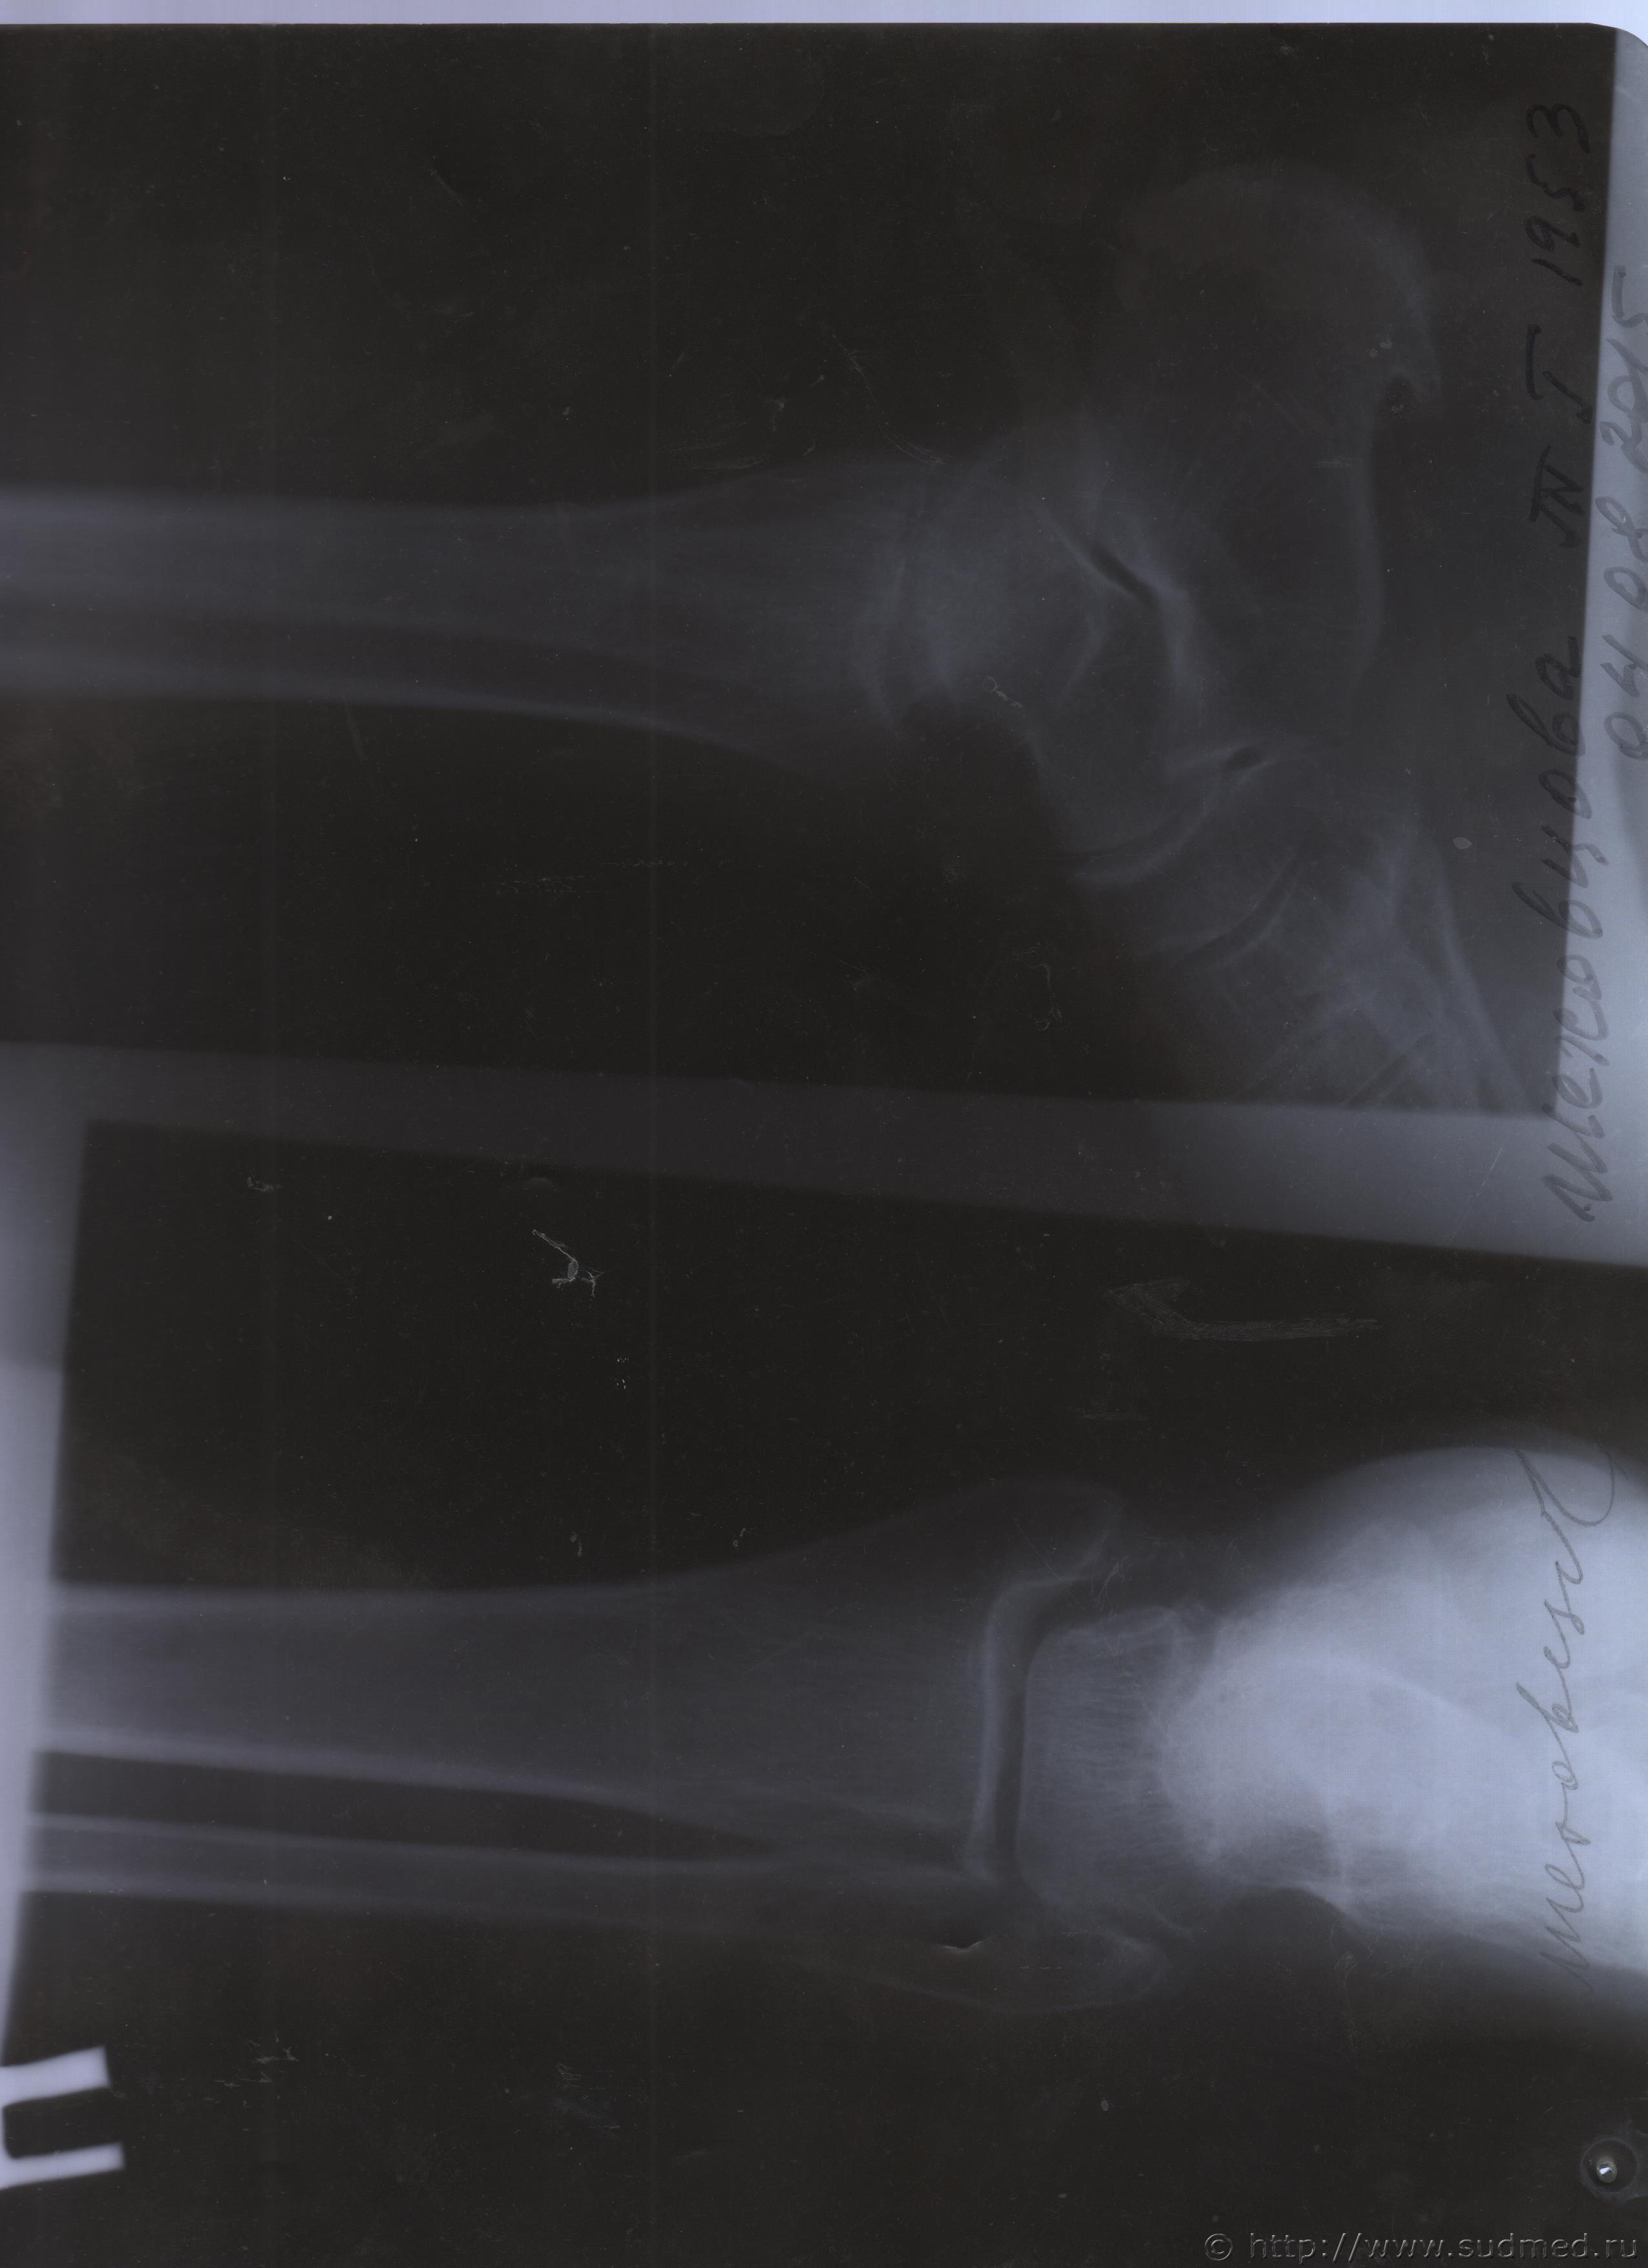

06.07.2015 г. при обращении в горбольницу мне выдали не описанный снимок( все рентгенологи были в отпуске) и справку № 4379 от 06.07.15 г. где диагноз: закрытый 2-х лодыжечный перелом правой голени без смещения. Копию справки прилагаю

За все 12 месяцев, что была на больничном, 8 раз делали снимки травмированной ноги и все заключения именно : «закрытый 2-х лодыжечный перелом правой голени без смещения».

После того, как был поставлен диагноз : «компрессионный перелом L2 позвонка поясничного отдела позвоночника». Амбулаторная мед карта, была украдена из кабинета врача травматолога. При восстановлении мед карты( в марте 2016 г.), врачом травматологом была взята копия справки от 06.07.15 г.из приемного отделения горбольницы. Справка № 4379 ( дубликат), диагноз : «закрытый 2-х лодыжечный перелом правой голени без смещения».

Уважаемые доктора, нужны ли снимки по перелому правой голени? и Заключения по МРТ и КТ.Ранее представляла результаты обследования...Сделала копию снимков по КТ и МРТ( только вот какого качества получились не знаю.)

Посмотрите, пожалуйста

Посмотрите, это снимки за 12 месяцев.

Уважаемая Татьяна! По представленным Вами снимкам ничего сказать нельзя: нет маркировки даты каждого снимка (поэтому, невозможно их сравнивать друг с другом и соотносить с датой травмы), исследование непосредственно пленок гораздо более информативно, чем анализ представленных изображений (детали костной структуры в зоне перелома практически не видны).

Рекомендую проконсультировать все эти снимки у высококвалифицированного рентгенолога. Далее - по ситуации, т.е. в зависимости от его мнения. В любом случае, есть формальные основания для назначения дополнительной экспертизы, т.к., судя по представленному Вами фрагменту заключения эксперта, на экспертизу не были предоставлены все мед.документы с данными о лечении предъявляемой травмы (Вы пишете, что рентгенограммы делались на протяжении 12 месяцев, полагаю, что Вы и врачами наблюдались в течение этого срока, т.е. велась мед.карта).